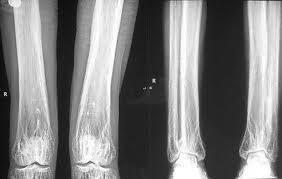

进行性骨干发育不良又称增殖性骨膜炎、对称性硬化性厚骨症、Engelmann病或Camurati-Engelmann病。为常染色体显性遗传性骨病。本病以全身性对称性骨发育异常为特点,骨骺一般正常,但亦可受累,进行性骨干发育不良怎么办?接下来跟大家分享下我的看法。

相关图片